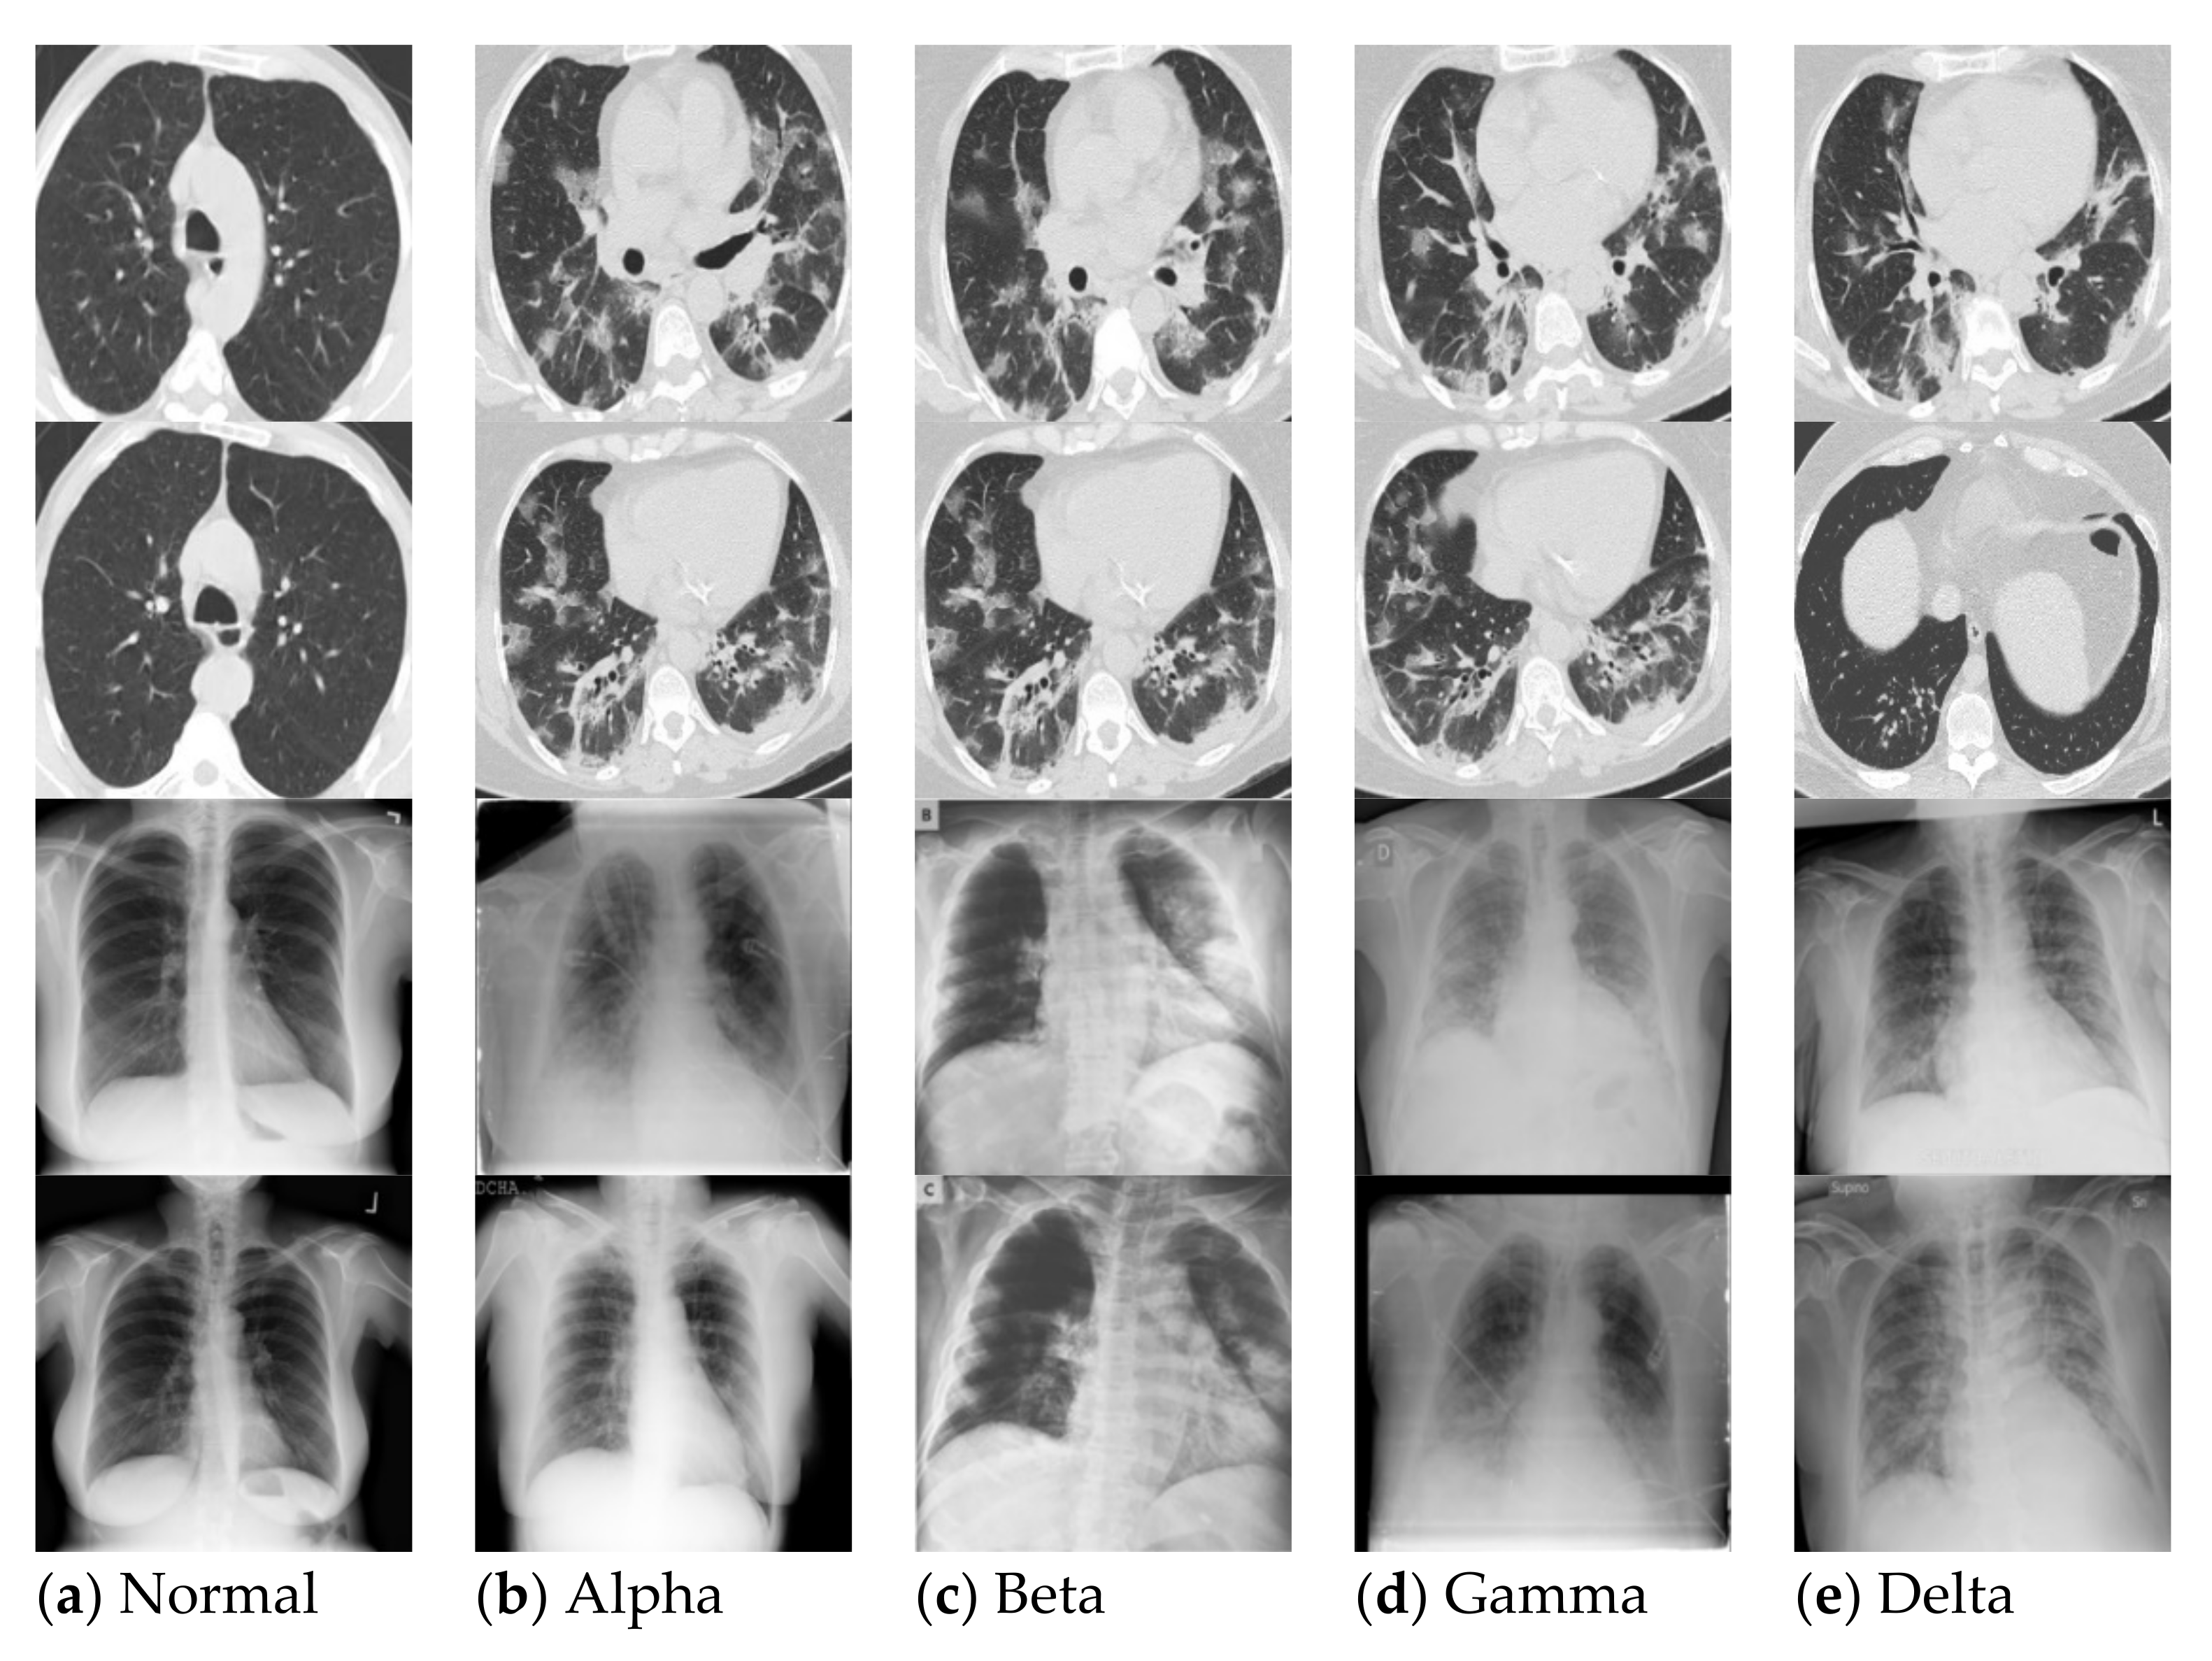

2. Literature Review

3.1.2. Sample Size of Chest X-rays and CT Scans